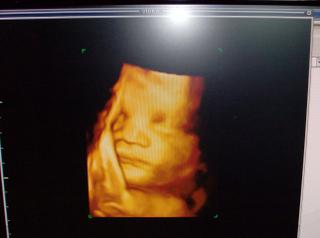

pamätate? 😵 😵 😵